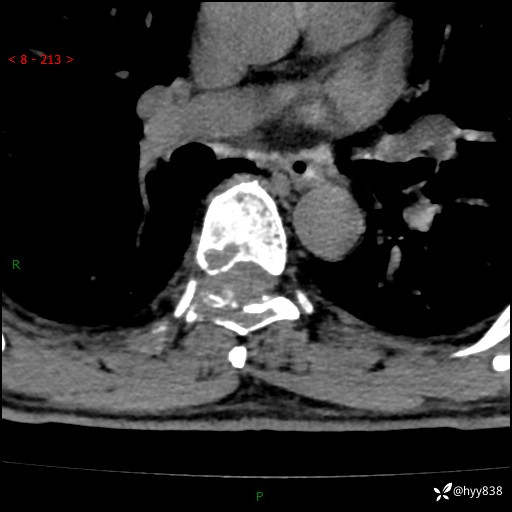

胸椎MRI平扫(sag T1WI+T2WI)

axi T2WI